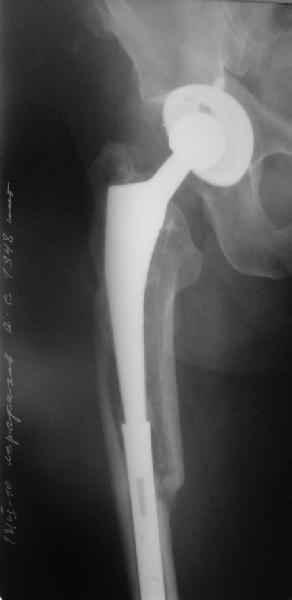

Уважаемые коллеги, в данном случае в лечении стандартного перипротезного перелома В2 Ванкуверской классификации (перелом вокруг ножки эндопртеза с потерей стабильности ножки при хорошем - не требующем пластики - качестве кости.Parvizi J, Rapuri VR, Purtill JJ, et al (2004) Treatment protocol for proximal femoral periprosthetic fractures. J Bone Joint Surg Am; 86-A Suppl 2:8-16)с успехом применён оригинальный, но малоизведанный способ лечения подобных повреждений. В результате и последующие рекомендации не могут быть стандартными. В подобных случаях, как это уже дискутировалось год назад, можно было выполнить ревизию длинной ножкой, во многом работающей как интрамедуллярный гводь + плюс кабель/серкляж в проксимальном отделе. Или, оставить имеющуюся ногу плюс длинная пластиа с кабелем/серкляжем, можно разными современными блокированными *примочками*. В таком случае при достижении консолидации пластина удаляется, тк при возникновении в будущем потребности в ревизии имеющийся дополнительный металл и без затруднит непростое вмешательство (кто пробовал, знает о чём я говорю). С длинной ногой, конечно, так же всё понятно. В данном случае мы имеем некую комбинацию, осложнённую отсутствием репозиции и фиксации в прошлом отломков вокруг ножки. Поэтому не каждый в данном случае рискнёт утверждать за счёт какого из компонентов системы - дистального либо проксимального обеспечивается стабильность. А если это и фиксация и за счёт ножки и за счёт гвоздя - каков баланс между данными компонентами в поддержании стабильности ситемы. То есть, я надеюсь, что дистального смещения ножки здесь не будет при условии сохранения как гвоздя, так и блокирующих винтов. При удалении же гвоздя возможна миграция ножки, только винтов - всей системы. Здесь же перелом (надеюсь, его не будет) блокирующих винтов может быть первым свидетельством механического неблагополучия системы... А так, помимо отличного результата этот случай так же косвенно подтверждает известную истину - Эндопротез, к сожалению, требует периодической замены. И выполняя фиксацию перипротезного перелома, а в последующем решая вопрос об удалении имплантатов, мы вынуждены думать и о функции сустава, и о том, как в будущем выполнить ревизию. Если ожидаемая продолжительность жизни пациента заставляет нас об этом думать. С уважением, Андрей

Дорогой Александр Николаевич! Спасибо, что держите всех нас в курсе.

Сейчас опорную нагрузку на бедро берет на себя система от бедренного компонента эндопротеза до проксимального винта в интрамедуллярном гвозде. Свидетельство тому - реакция кортикала утолщением вокруг того самого винта. Таким образом вся кость от верхушки б.вертела до проксимального винта не испытывает физиологической осевой нагрузки. Результатом этого могут стать следующие последствия друг друга не исключающие: 1) все будет хорошо до перелома опорной системы по винту(ам) или в месте соединения штифта с ножкой или еще где-либо, 2) исключенная из-под нагрузки кость будет терять в количестве и качестве, что не очень (или очень не) хорошо для возможных будущих ревизий (тьфу-тьфу!!!).

Уважаемый Александр Николаевич,

Как Вы знаете, мы имеем негативный опыт подобной операции (перелом ножки эндопротеза на месте соединения со штифтом), но тем не менее хотелось бы сказать следующее. На мой взгляд,выполняя такую фиксацию, мы становимся заложниками сохранения всей этой мегаконструкции на долгое время, если не на всю жизнь. Эта система работает уже как единое целое. Рефиксации ножки эндопротеза не произошло, при удалении гвоздя может развиться вторичная нестабильность, скорее всего со временем произойдут дистрофические изменения в кости за счет шунтирования нагрузки. Поэтому есть смысл отследить очень тщательно р-ты этих операций, прежде чем они войдут в повседневную практику, думаю что показания к ним будут весьма ограничены. Пару раз попробовали "пошалить", собрали бедро на бесцементной ножке у пожилых б-х дабы не утяжелять вмешательство. В одном случае - срослось и ножка получила стабильность, в другом - потребовалось реэндопротезирование, но со значительно меньшей травмой. т.к.бедро срослось.